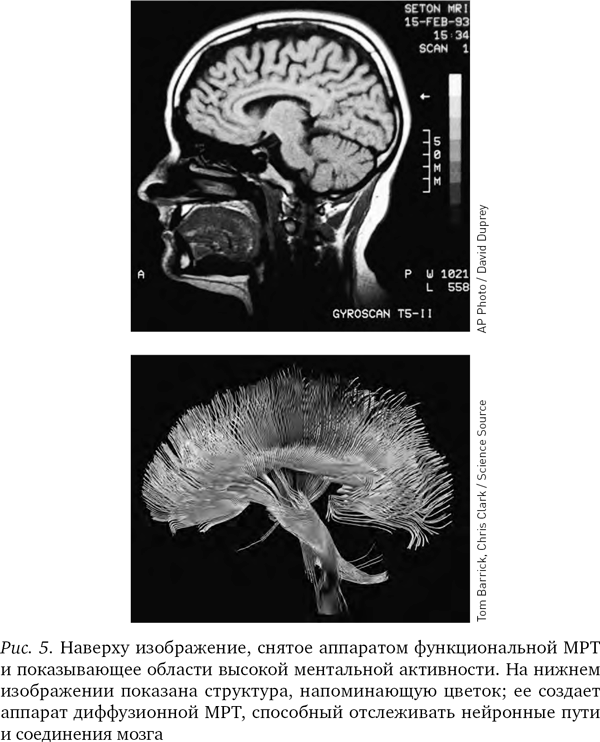

Это описание мозга примерно отражает состояние науки в 1980-е гг. Однако в 1990-е гг., когда развитие физики привело к появлению новых технологий, механизмы мышления стали изучаться в мельчайших подробностях, а нейробиологию ожидал бум научных открытий. Одной из рабочих лошадок, обеспечивших успех этой революции, стал аппарат МРТ.

Радиоволны – один из видов электромагнитного излучения – способны проходить сквозь живую ткань, не причиняя ей вреда. Аппараты МРТ, используя это свойство радиоволн, исследуют нашу черепную коробку. Технология магнитно-резонансного сканирования позволяет получить великолепные фотографии того, что прежде никто не рассчитывал когда-либо увидеть и запечатлеть: внутреннее устройство мозга и его деятельность в процессе работы, при различных эмоциях и при получении информации от органов чувств. Наблюдая танец крохотных огоньков в аппарате МРТ, можно проследить за движением мысли внутри мозга. Мозг при этом напоминает часы с открытым механизмом, где видно, как все устроено, и можно наблюдать за ритмичным движением крохотных рычажков и шестеренок.

Вначале, когда аппараты МРТ только появились, они могли показывать структуру мозга лишь в статике и на различных его участках. Однако в середине 1990-х гг. был изобретен новый вид МРТ, получивший название функциональной магниторезонансной томографии, или фМРТ; и теперь аппараты уже различали присутствие кислорода в крови в сосудах мозга. (Иногда ученые обозначают маленькой буквой перед аббревиатурой МРТ тип аппарата, но мы будем использовать аббревиатуру МРТ во всех случаях.) На полученных при помощи МРТ изображениях не виден непосредственно ток электричества в нейронах, но поскольку без кислорода нейроны не получат энергии, насыщенная кислородом кровь косвенно указывает на поток электрической энергии в нейронах и наглядно показывает, как различные области мозга взаимодействуют между собой.

МРТ-изображения опровергли представление о том, что мышление сосредоточено в едином центре. Напротив, можно видеть, что в процессе мышления электрическая энергия циркулирует по различным частям мозга. Отслеживая путь, который проходят мысли в голове человека, МРТ-аппараты помогли пролить свет на природу болезней Альцгеймера и Паркинсона, шизофрении и других психических заболеваний.

Серьезным преимуществом МРТ-аппаратов является то, что они могут с высокой точностью выделять крохотные, вплоть до десятых долей миллиметра, участки мозга и рассматривать их отдельно. МРТ-изображение – не просто точки на двумерном экране (пикселы), а точки в трехмерном пространстве (вокселы): в результате исследования мы получаем яркое трехмерное изображение мозга, сложенное из десятков тысяч цветных точек.

Различные химические элементы реагируют на разные частоты радиоволн по-разному, поэтому мы можем, изменяя частоту волны, определять, где какие элементы находятся. Как уже отмечалось, при фМРТ в основном отслеживаются атомы кислорода в крови и измеряют кровоток, но вообще-то аппарат МРТ можно настроить на любое вещество. В последнее десятилетие появилась новая разновидность МРТ – диффузионно-тензорная; она отслеживает движение воды в объеме мозга. Вода в мозге следует по нейронным путям, поэтому диффузионно-тензорная томография позволяет получить красивые картинки, напоминающие переплетение растущих в саду лиан. Теперь ученые могут мгновенно определить, как части мозга связаны между собой.